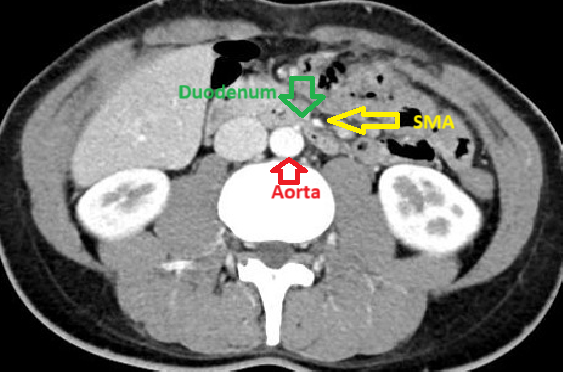

Img | UGI series: No passing of radiocontrast beyond 3rd part of duodenum CT: Duodenal stenosis between aorta and SMA, proximal duodenal dilatation |

• 실제로 UGI series에서 바륨 조영제가 마치 duodenum을 칼로 자른 듯이 3rd part의 특정 지점을 넘어가지 못하고 있다. CT에서도 aorta(L-spine 바로 앞의 밝은 원)와 SMA(aorta에서 2시 방향에 있는 같은 음영의 원/타원) 사이에 duodenum이 눌려있는 것이 보이며, 이로 인해 우측의 proximal dilatation이 발생한 것도 확인된다.